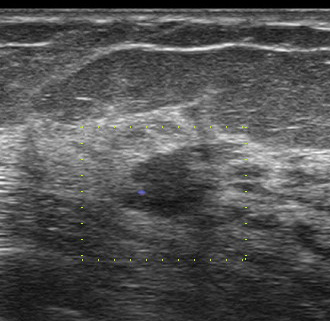

これが検診時の画像

私カテゴリーでは「私cat.6 乳癌の可能性がかなり高い」

例)スピキュラはないけど不整形、境界不明瞭

♯ちなみに一般的なカテゴリー(1~5)では4となります。